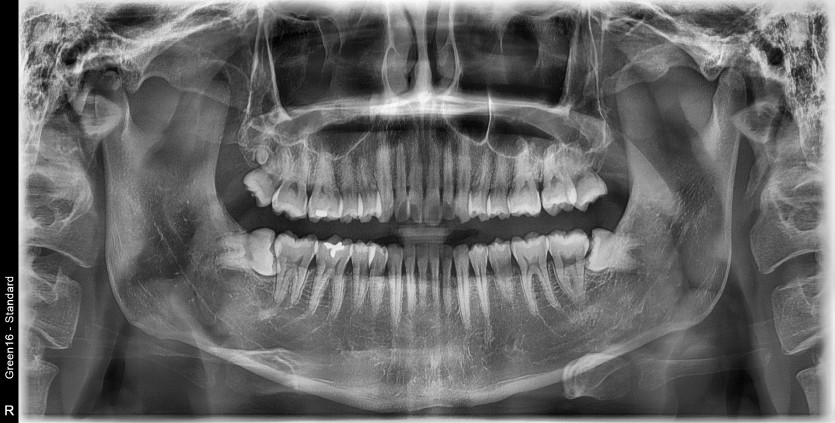

#18,28,38,48 사랑니 발치 (#19과잉치 포함)

구강 외과 전문의가 당일 발치했습니다.